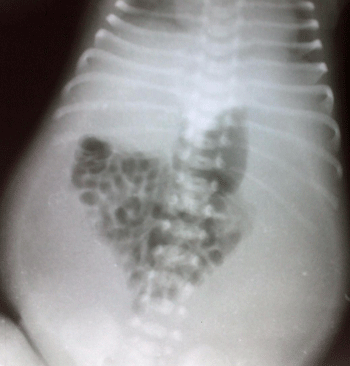

A 2-day-old male neonate, born by spontaneous vaginal delivery at home, presented with failure to pass meconium, vomiting and abdominal distention since birth. The history of polyhydramnios was present. Antenatal anomaly scan was reported normal. On general physical examination, patient had weak cry, feeble peripheral pulses, and respiratory rate of 42 per minute. The birth weight was only 2.5 kg. On examination, abdomen was symmetrically distended with tenderness. Routine lab tests were normal. The abdominal x-ray (Fig. 1) showed bowel gas shadows gathered in the center of abdomen and seemed to be surrounded by homogenous opacity. The abdominal ultrasound showed free fluid present in peritoneal cavity. We suspected complicated meconium ileus preoperatively.

To conclude, abdominal cocoon is extremely rare in neonates and infants. Crowding of bowel gas shadows with peripheral homogenous opacity on plain radiograph may raise a suspicion of abdominal cocoon. Meconium peritonitis may be enlisted in the etiology of abdominal cocoon.

Figure 1: Abdominal radiograph. |